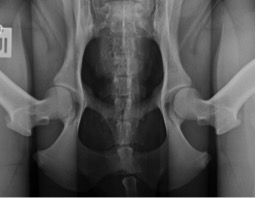

Für das PennHIP® Verfahren werden drei Röntgenaufnahmen angefertigt:

Bei der Distraktionsaufnahme wird ein sogenannter Distraktor zwischen die Beine des Tieres gelegt. Wenn der Untersucher die Beine des Hundes gegen den Distraktor drückt, wird der Oberschenkelkopf aus der Hüftpfanne „herausgezogen“. Je weiter das möglich ist, desto lockerer ist die Hüfte und desto größer die Wahrscheinlichkeit, dass ein Hund an einer HD leiden wird. Das Maß für die Lockerheit des Hüftgelenks ist dabei der Distraktionsindex (DI).

links: komprimiertes Hüftgelenk

rechts: distrahiertes Hüftgelenk

Berechnung des Distraktionsindex

(Quelle: AIS PennHIP®)

Der Distraktionsindex wird berechnet, indem bei der Distraktionsaufnahme die Entfernung zwischen dem Mittelpunkt des Oberschenkelkopfes und dem Mittelpunkt Hüftpfanne gemessen und diese Strecke durch den Radius des Oberschenkelkopfes geteilt wird. Dabei kann der Index von 0 bis 1,0 betragen. Bis zu einem Distraktionsindex von 0,3 ist die Wahrscheinlichkeit, dass sich das Krankheitsbild einer HD entwickelt, äußerst gering. Bei Rassen wie z.B. dem Barsoi oder dem Greyhound ist ein solcher DI üblich. Bei diesen Rassen entwickelt sich im Verlaufe des Lebens im Regelfall nicht das Krankheitsbild einer HD.